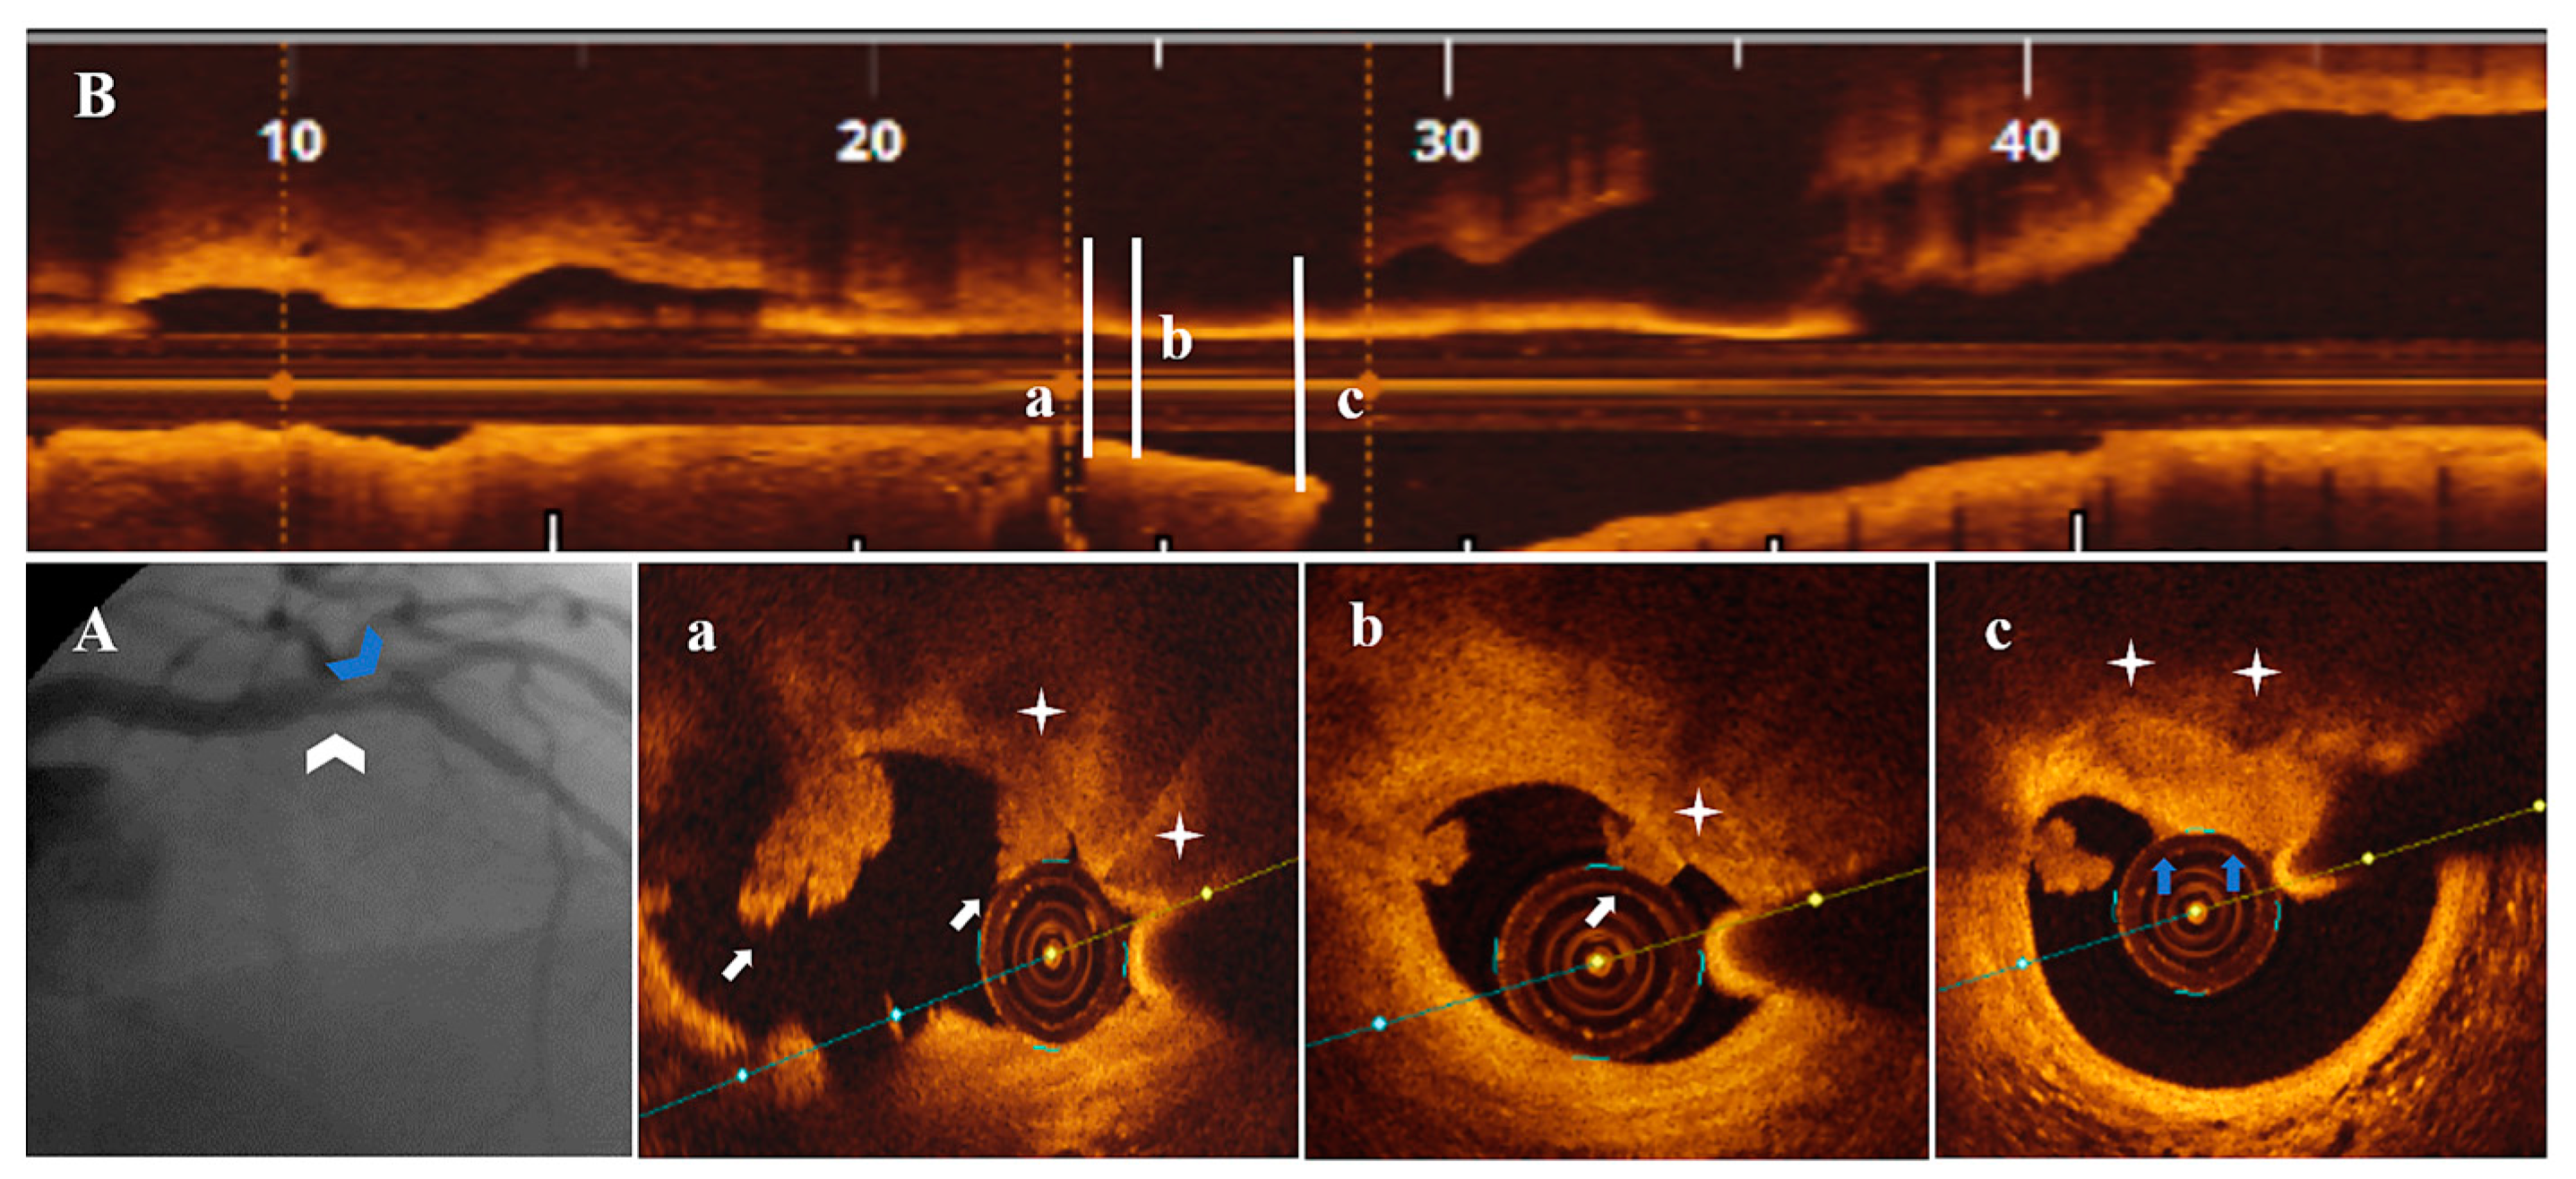

Figure 1.

A 74-year-old patient presenting with UAP. (A) CA—borderline proximal LAD (white arrowhead) and significant proximal second diagonal (blue arrowhead) stenoses. (B) OCT—LAD plaque longitudinal view. (a) Significant (area stenosis = 73.9%) stenosis after the origin of the second diagonal. (b–e) SCP (white star) presenting PE with white thrombi (white arrow) in the proximal plaque segment. (C) CA—final result after PCI with 2.75 mm DES/LAD and plain old balloon angioplasty/second diagonal.